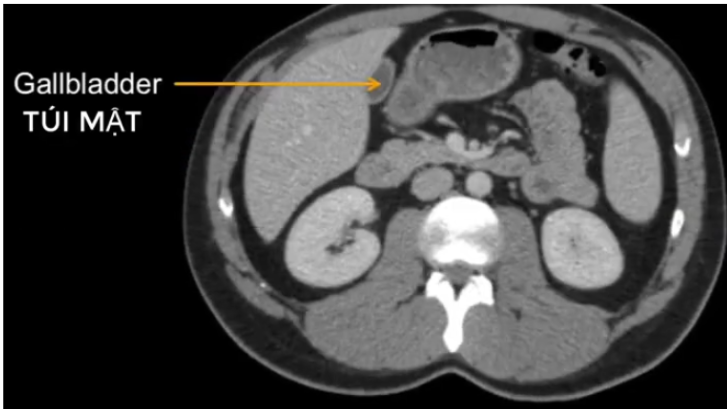

a) Túi mật TA viết là?